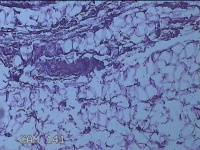

外阴部包块

性别

女

年龄

37岁

临床诊断

皮脂腺囊肿

一般病史

外阴部起包块一月余。

标本名称

大体所见

灰白暗红色包块2.3x1.8x0.8cm一个,表面糜烂,切开包块呈实性,切面灰白淡黄色,质软。

图4

有那么点像脂肪瘤。